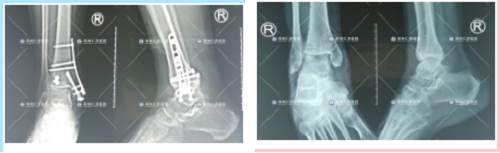

取内固定前、后

次治疗前、手术后,恢复良好

历时近4个小时,谷国俊副主任带领团队成功为其进行了右内踝部粉碎性骨折并神经损伤、右后踝骨折切开复位内固定术,术后转入病房给予精细观察和治疗。

谷国俊副主任说,“因为是粉碎性骨折,术中需要将每一块碎了的骨骼面精准对齐,这样才能保障康复后的效果,因为是粉碎性骨折,碎的块数比较多,无疑就增加了手术的难度”。